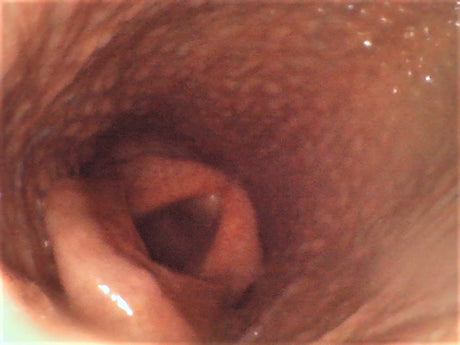

Replaceable Probe Camera for VE-8150 Veterinary Endoscope